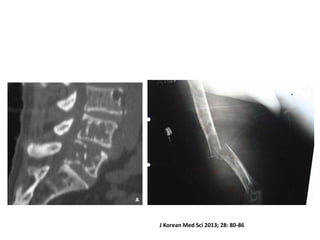

Objetivo

• Mostrar respuesta de bortezomib +

quimioterapia temprana en supervivencia de

pacientes con mieloma múltiple

Material y

Métodos

• Evaluación de respuesta a los 4 ciclos

• Criterios de valoración: comparación supervivencia libre de

progresión (SLP) y la supervivencia global (SG) entre grupo de

buena respuesta (grupo A) y grupo de respuesta pobre (grupo

B).

Resultados

• 129 pacientes

• La SLP a 3 años grupos A y B fue:55,6% y

18,4%, respectivamente (P <0,001).

• La SG a 3 años grupos A y B fue: 65,3% y

52,9%, respectivamente (P = 0,078).

Korean Med Sci 2013; 28: 80-86

J Korean Med Sci 2013; 28: 80-86